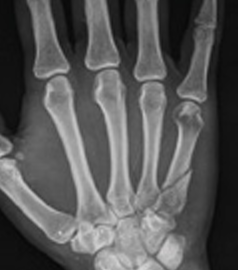

Suggest X-ray

Choosing the right hand therapist starts with them being able to read your X-rays and then fabricate the right brace for you. The therapists at Action Rehab Hand Therapy Clinic are experienced in assessing and reading X-rays.